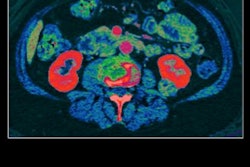

The team examined the knees of 27 patients using dual-energy CT in three planes: axial, sagittal, and oblique sagittal images to which a bone-removal algorithm and tendon-specific color mapping had been applied. The results showed that 16 patients had confirmed ACL tears, while 11 others had no history of trauma.

Two experienced readers, a musculoskeletal radiologist and a senior radiology resident, reviewed all the images. The radiologist achieved a 94% accuracy rate in identifying tears versus 87% for the resident.